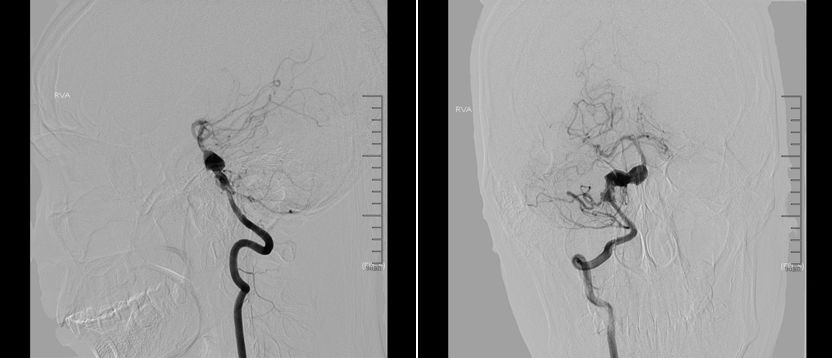

术前右椎动脉造影显示:基底动脉中下段夹层动脉瘤。

术前右椎动脉3D造影

术前左椎动脉造影显示:基底动脉中下段夹层动脉瘤,左侧小脑后下动脉夹层动脉瘤。